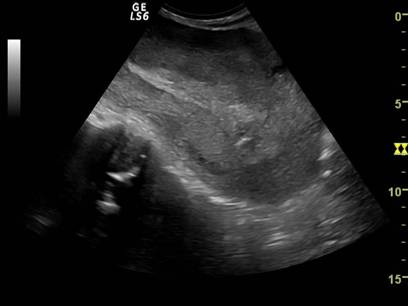

Fig, nr.334 Lauzie ziua a II a dupa nastere spontana la termen, cavitate uterina cu minim continut